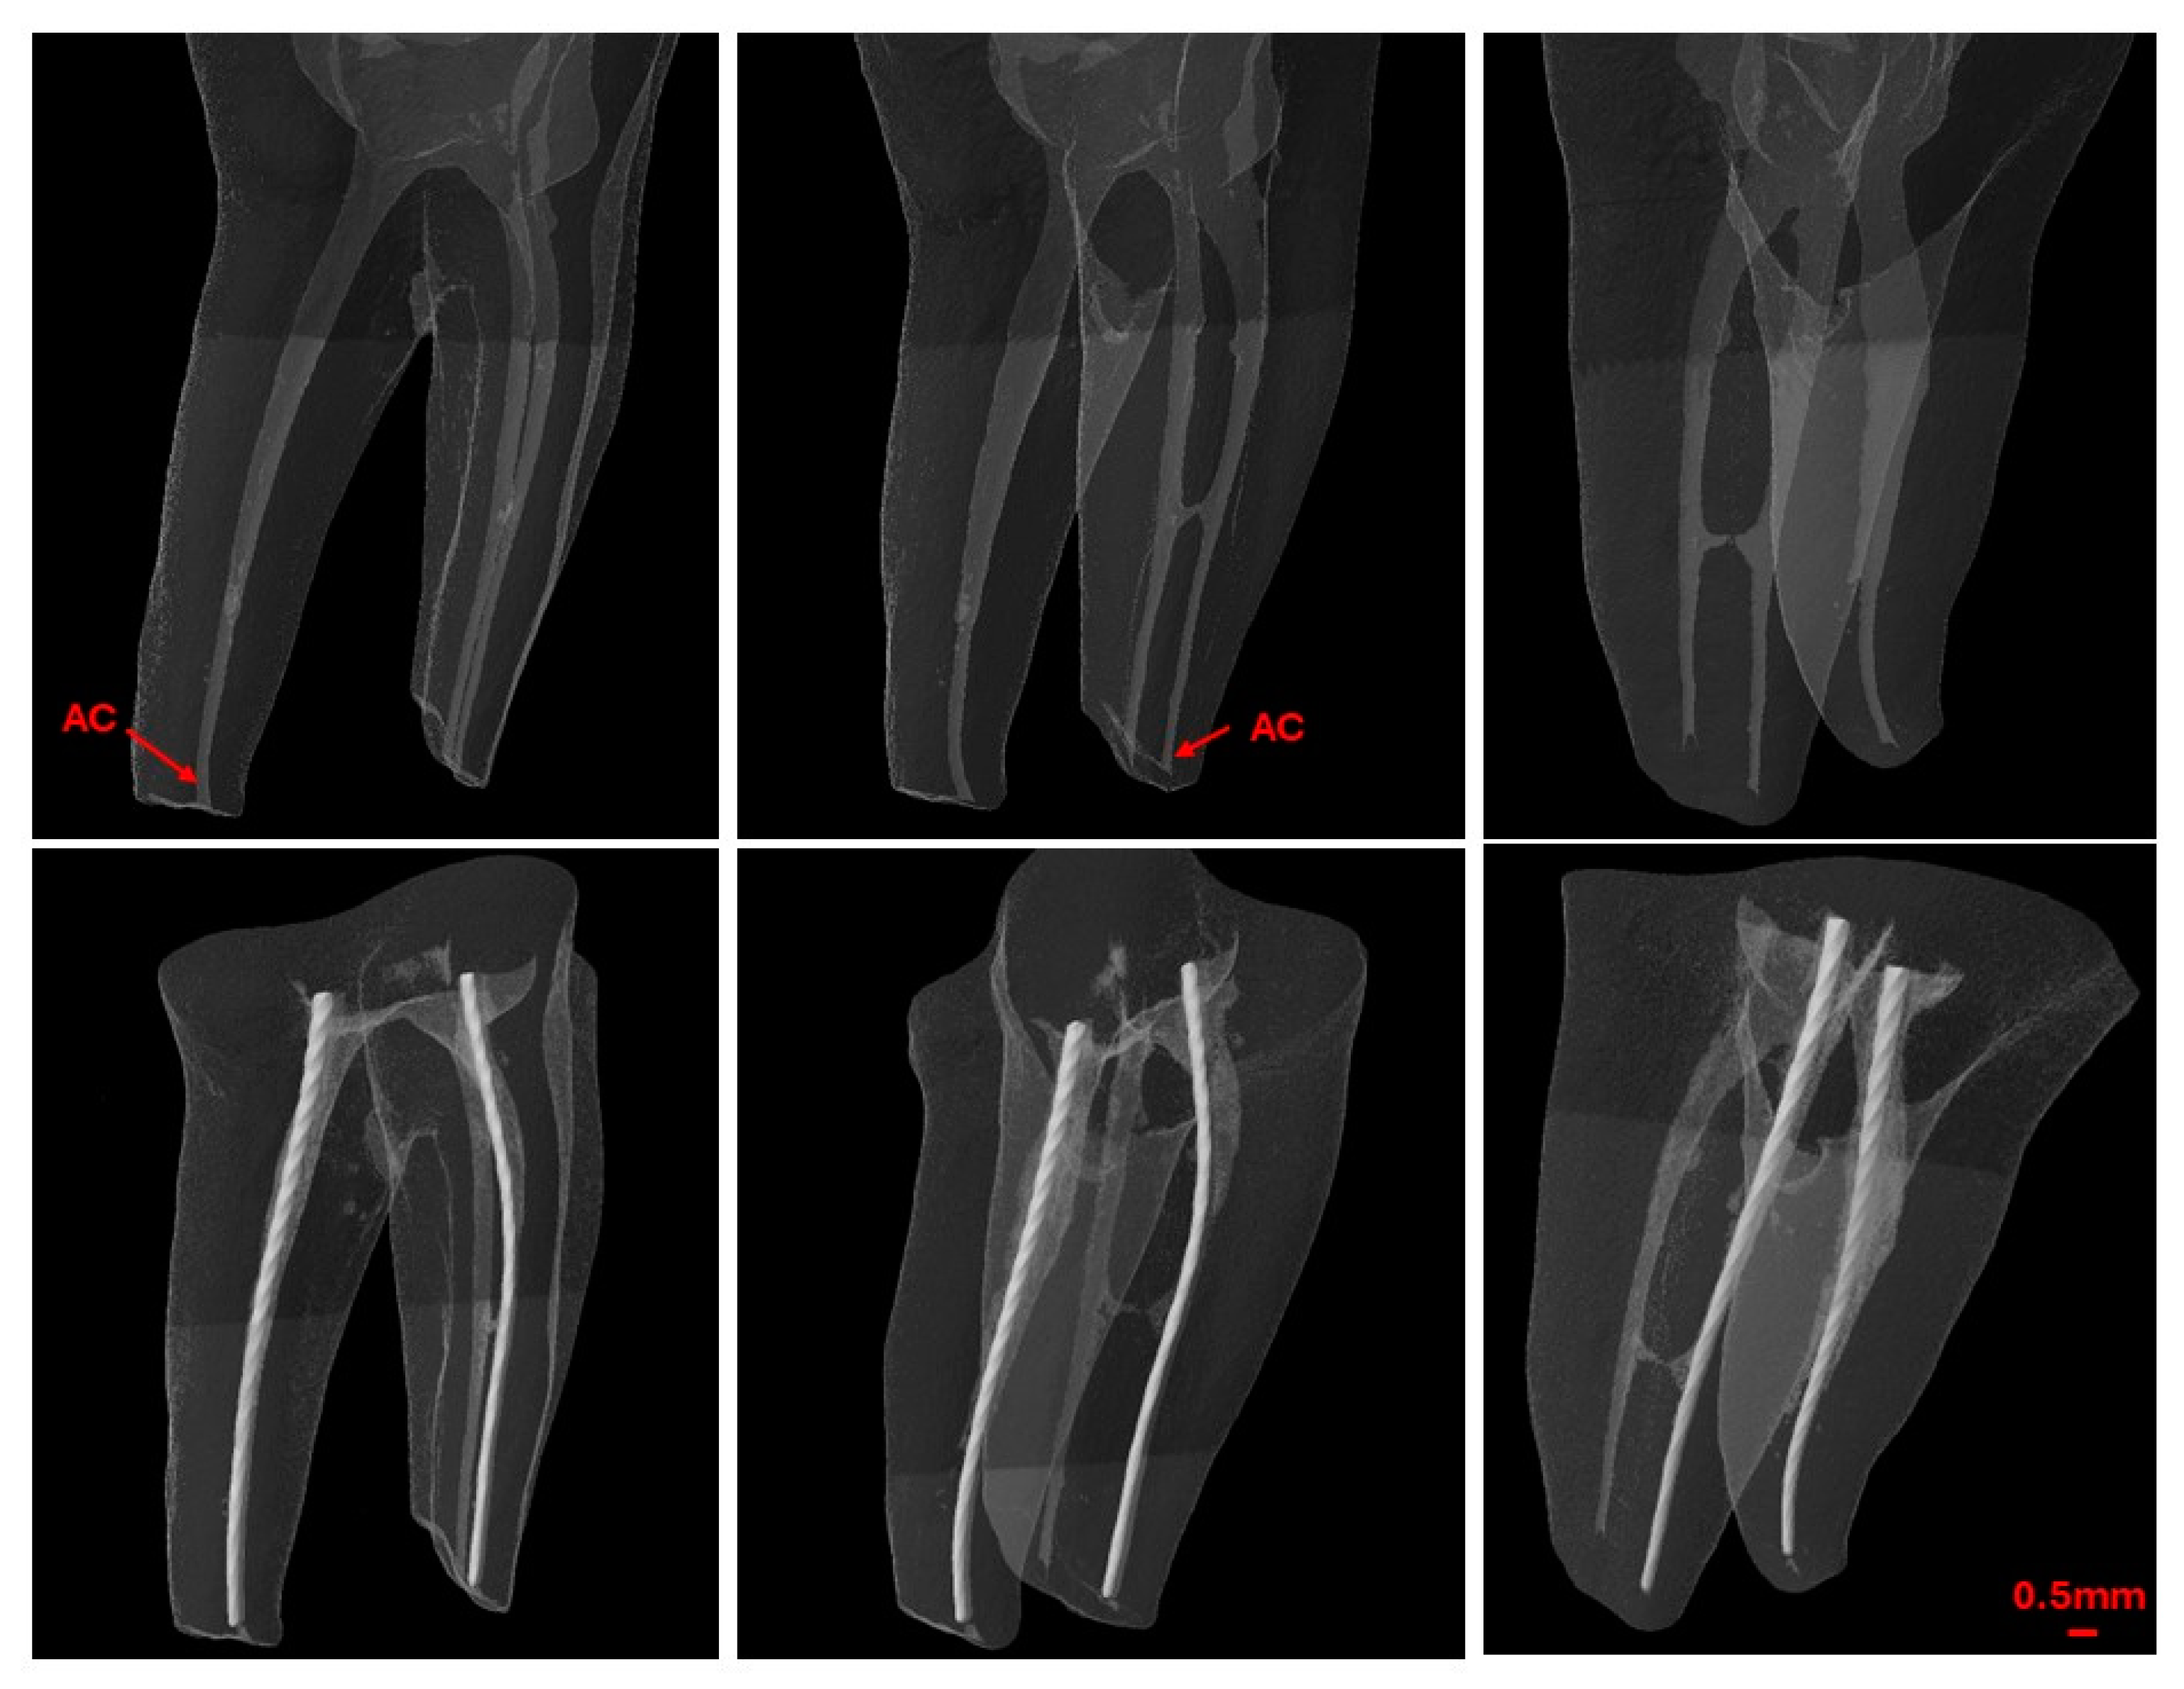

2.6. Second Scan—Post-WL Measurement

After establishing the WL using EAL, a second scan was conducted with the endodontic file fixed within the canal (Figure 4). The pre- and post-scan datasets were co-registered, and the distance between the tip of the endodontic file and the previously identified AC was calculated and recorded as positive or negative values relative to the AC.

Figure 4.

Pre- and post-working length measurement micro-CT scans.

For clarity and accuracy assessment, the recorded measurements falling within 0.1–0.5 mm from the AC were categorized as ‘close’. Measurements extending beyond the tolerance level towards the major foramen were categorized as ‘beyond’, otherwise they were classified as ‘far’.